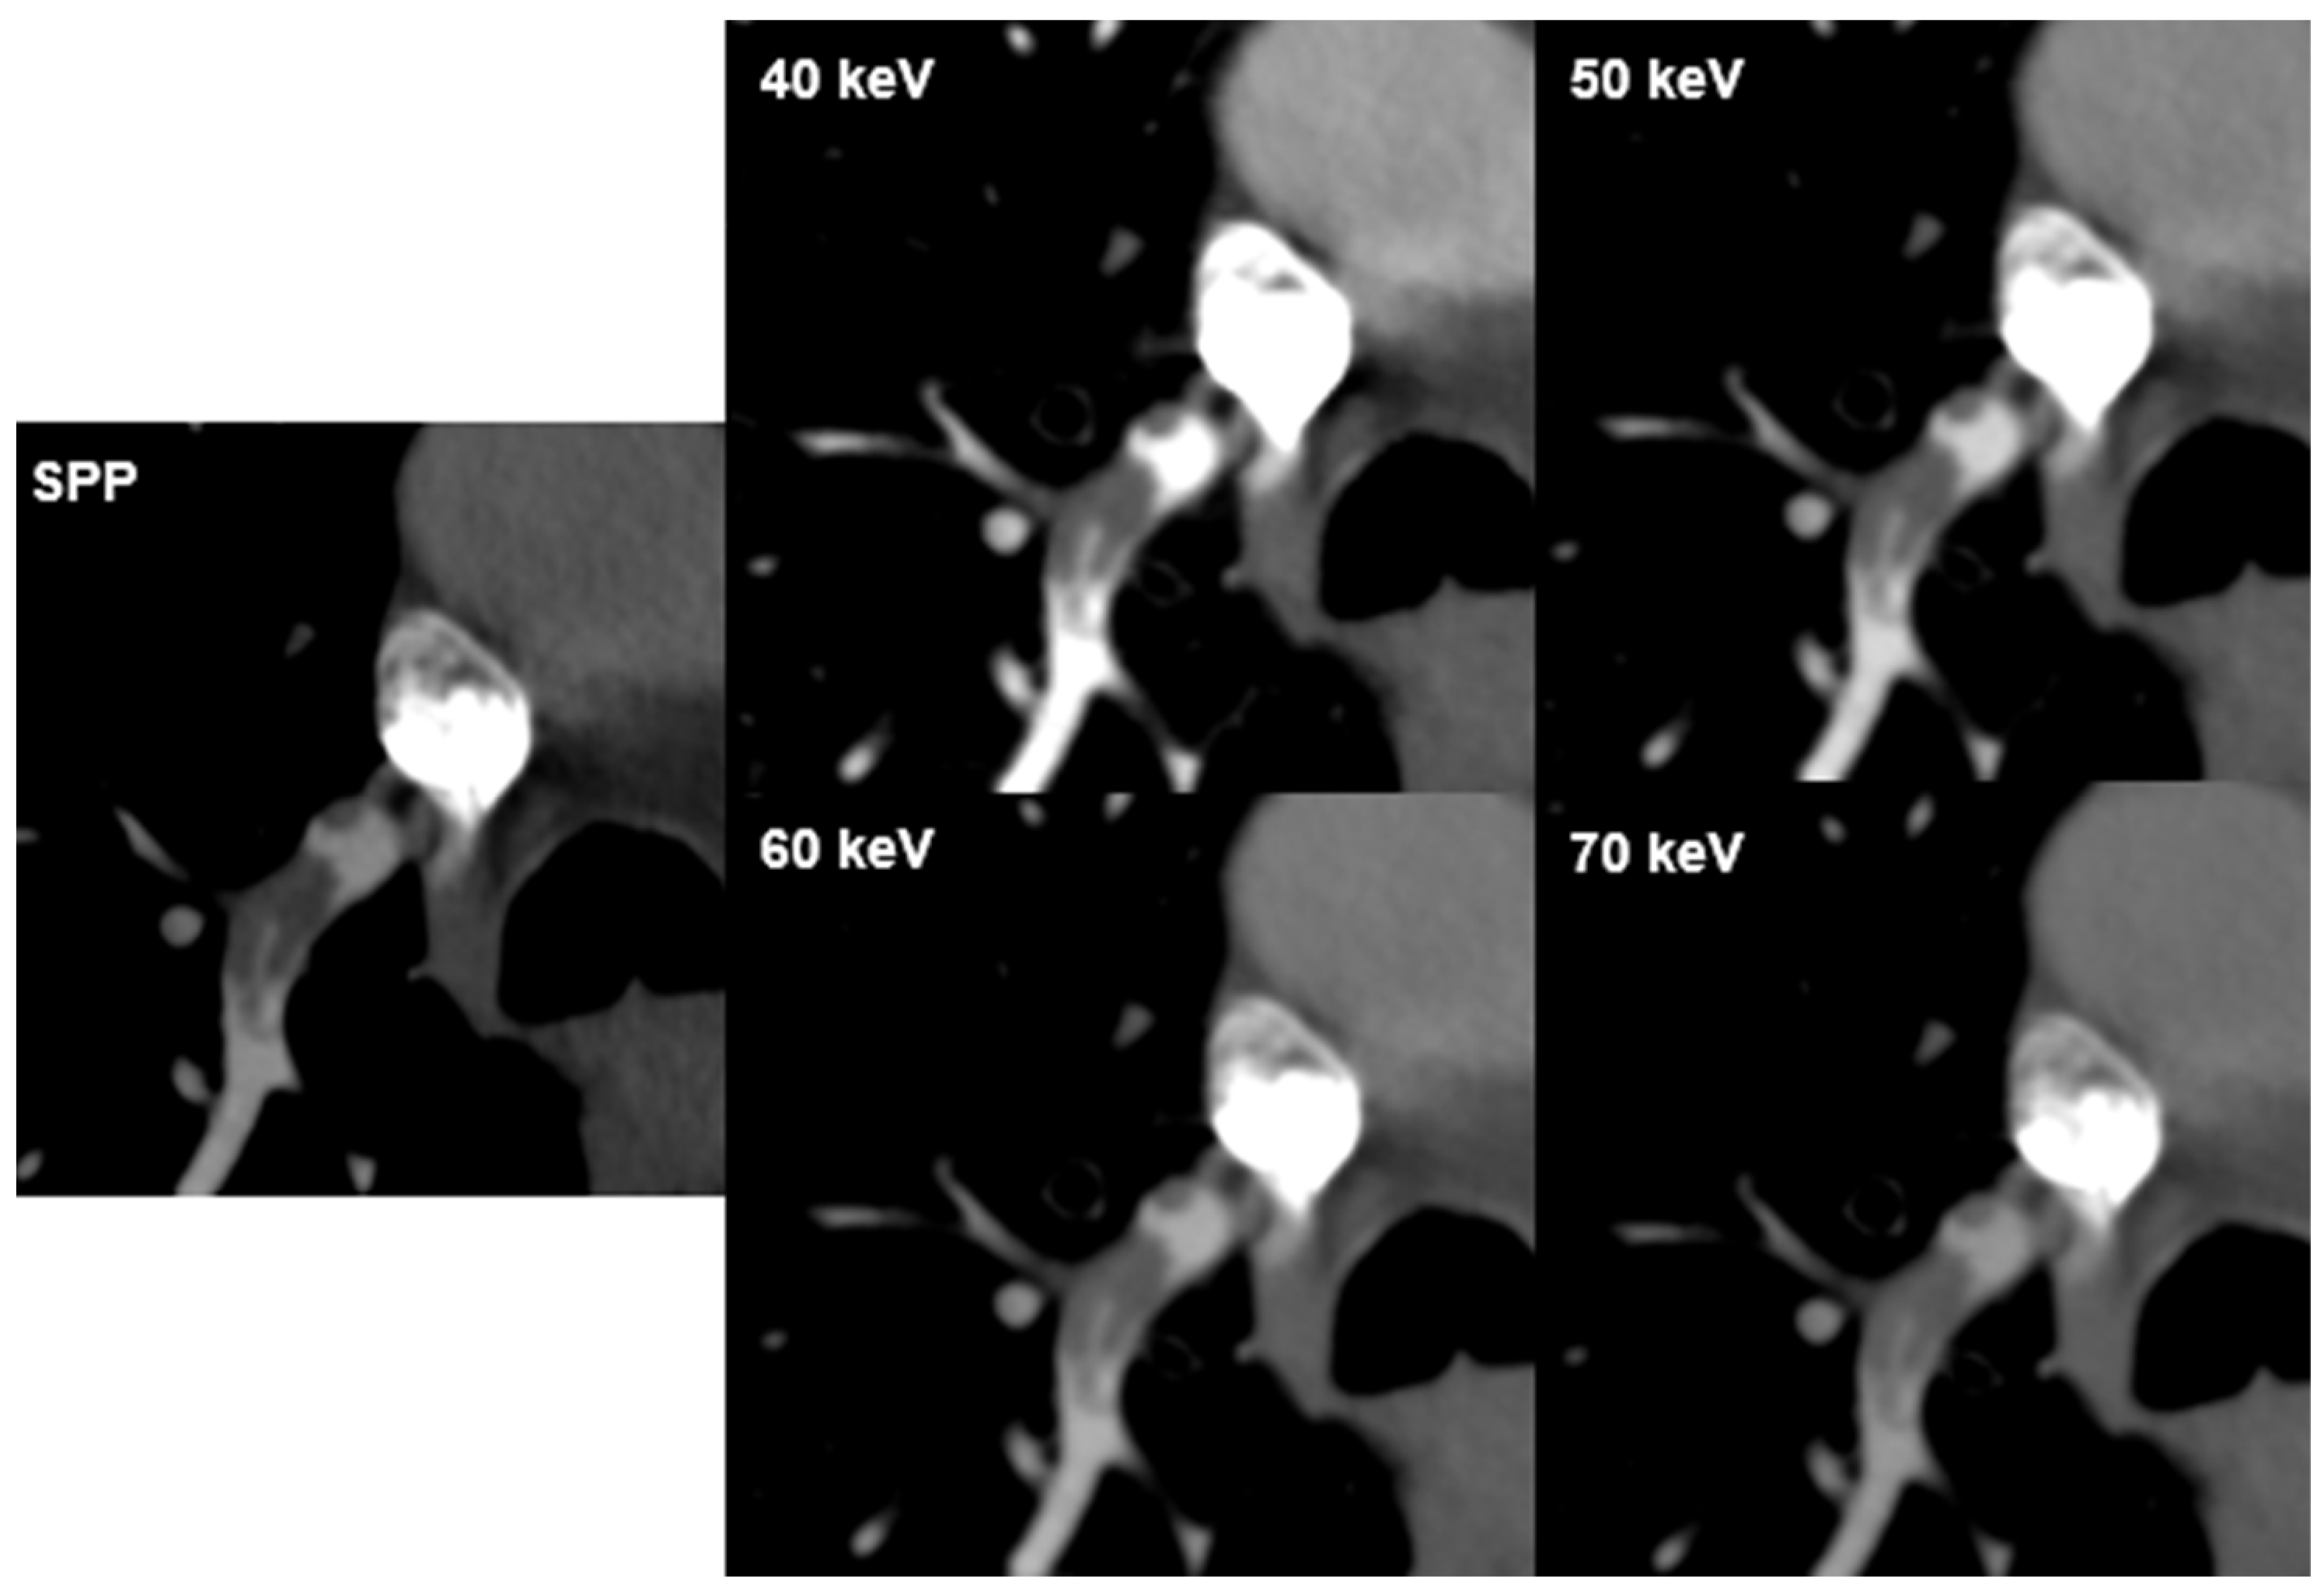

| PE visualization | 40 | 4.5 [3–5] | 4.4 [3–5] | 0.515 | 0.001 | 35 |

| 50 | 4.7 [4–5] | 4.7 [4–5] | 0.612 | 0.000 | 35 | |

| 60 | 4.1 [3–5] | 3.8 [3–5] | 0.392 | 0.001 | 35 | |

| 70 | 3.7 [2–5] | 3.5 [2–4] | 0.373 | 0.001 | 35 | |

| SPP | 3.8 [2–5] | 3.4 [2–4] | 0.373 | 0.000 | 80 |